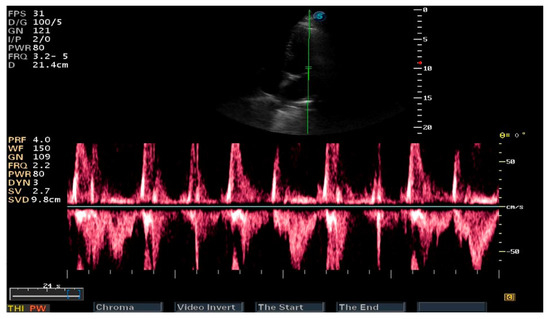

| IVS (cm)—PLAX | 1.93 | 1.27 | 1.2 |

| PLVW (cm)—PLAX | 1.38 | 1.16 | 1.05 |

| RV diameter (cm)—PLAX | 4.1 | 3.7 | 3.59 |

| LVTDV (ml/m2bs)—A4C | 114.5 | 100.7 | 90.8 |

| LVTSV (ml/m2bs)—A4C | 63.8 | 54.07 | 50.9 |

| LVEF (%)—A4C | 43 | 46 | 44 |

| RVTDV (ml/m2bs)—A4C | 33.3 | 50.5 | 22.2 |

| RVTSV (ml/m2bs)—A4C | 15 | 20.6 | 13.5 |

| LATSV (ml/m2bs)—A4C (*) | 38.2 | 44.5 | 37.1 |

| RATDS (ml/m2bs)—A4C (*) | 22.7 | 50 | 10.4 |